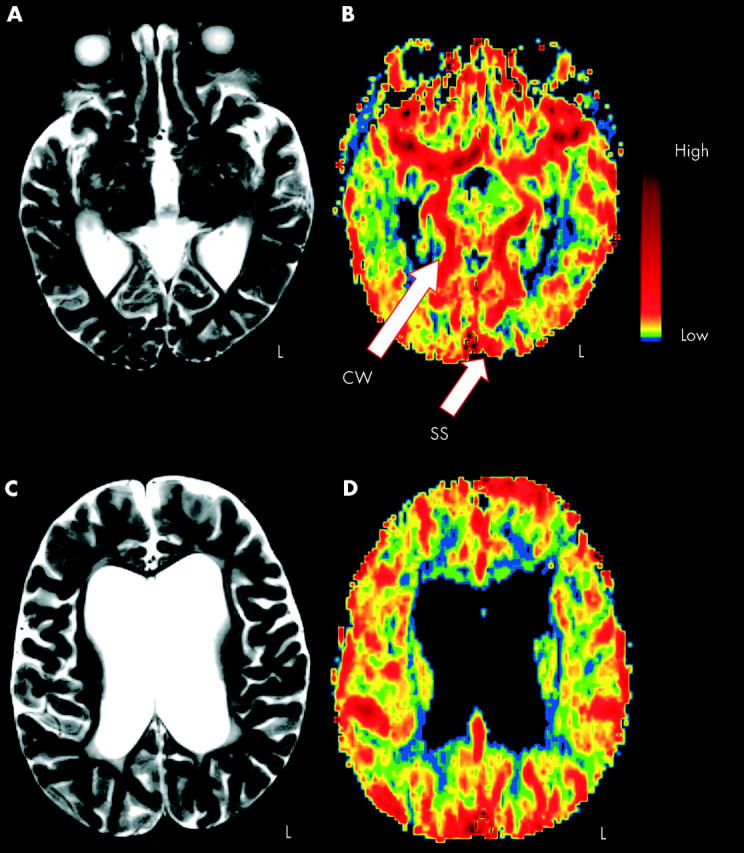

Figure 1 .

Magnetic resonance (MR) structural-functional comparison. Conventional T2 weighted images (A and C) versus MR perfusion images (B and D); axial sections obtained at two levels of the brain. Functional data are displayed using a non-linear colour scale. CW, Circle of Willis; SS, sagittal sinus; L, left. See text for further details.